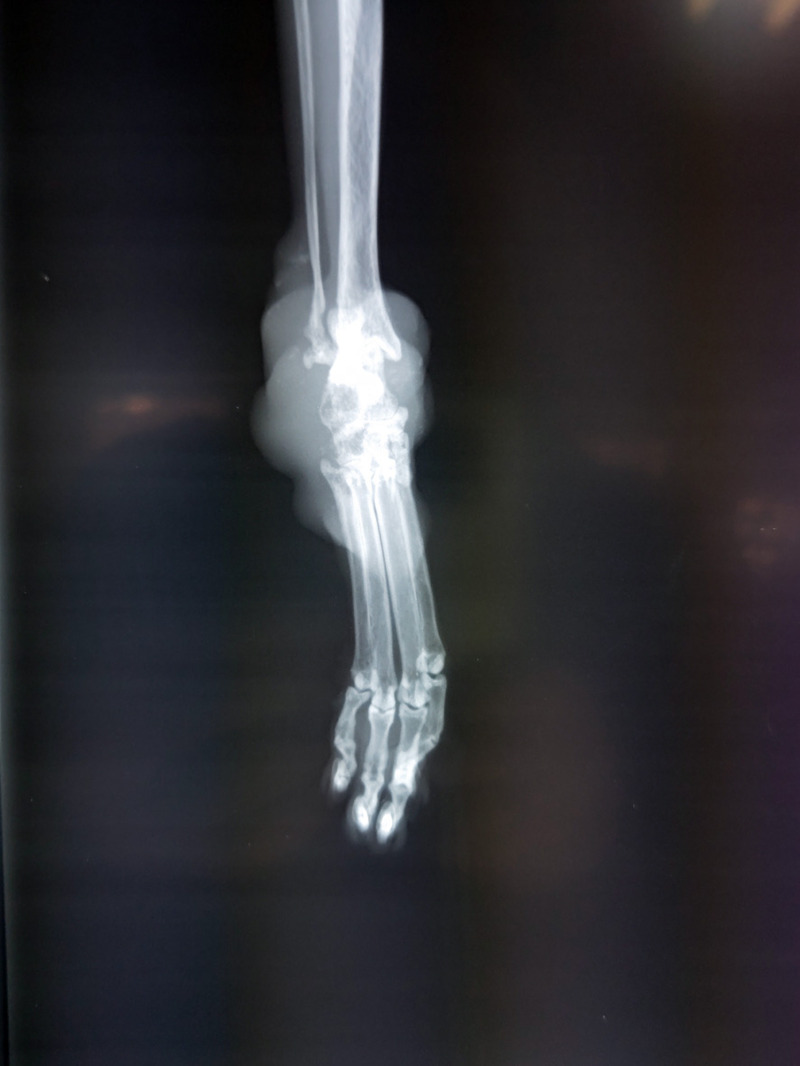

甲状腺のお薬は5年以上

てんかんのお薬も飲むことになった